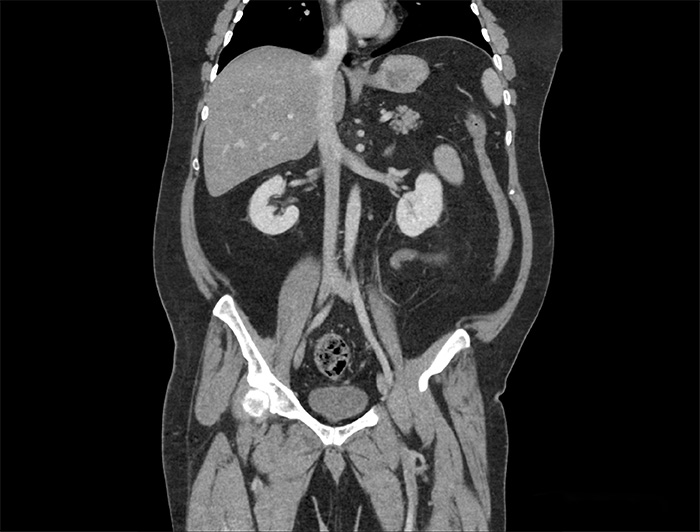

Image Courtesy Of Saint Joseph's Regional Medical Center, Indiana

All uCT systems are fully equipped to support a wide range of patient populations and clinical applications—from pediatric and bariatric cases to angiography and cardiology. Every system includes advanced applications and post-reconstruction analysis tools, helping you expand clinical capabilities with confidence.